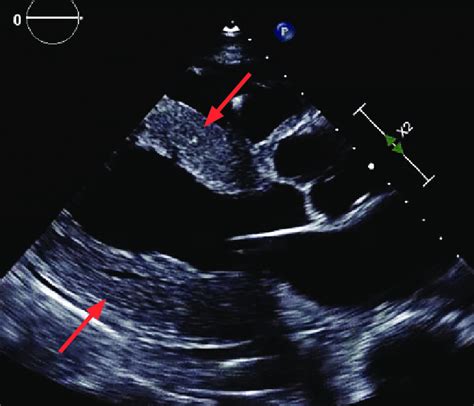

The long axis view, especially the parasternal long axis (PLAX) view, is a cornerstone in echocardiography. Guys, think of it as the money shot! This view allows us to visualize key structures like the left ventricle, right ventricle, aortic valve, mitral valve, and the left atrium all in one go. With this comprehensive view, clinicians can assess heart valve function, measure chamber sizes, and evaluate the overall systolic and diastolic function of the heart. For example, being able to see the mitral valve clearly helps in diagnosing mitral stenosis or regurgitation. Similarly, a good view of the aortic valve is essential for identifying aortic stenosis or aortic insufficiency. Furthermore, the long axis view is crucial for detecting structural abnormalities such as hypertrophic cardiomyopathy or dilated cardiomyopathy. By measuring the thickness of the ventricular walls and assessing the size of the chambers, clinicians can gain valuable insights into the heart’s condition. In emergency situations, the PLAX view can quickly provide information about pericardial effusions or cardiac tamponade, guiding immediate treatment decisions. So, yeah, mastering this view is a big deal for accurate diagnoses and effective patient care.

Alright, let’s get down to the nitty-gritty of long axis view echo probe position . The standard approach starts with placing the probe in the third or fourth intercostal space, just to the left of the sternum. Now, here’s the kicker: the orientation marker on your probe (usually a notch or a light) should be pointing towards the patient’s right shoulder. This is crucial because it aligns the ultrasound beam in the correct plane to capture the long axis view of the heart. Once you’ve placed the probe, start by fanning and tilting it slightly. Fanning involves making small, sweeping motions from side to side, while tilting means angling the probe up or down. These subtle adjustments can make a huge difference in image quality. You’re essentially hunting for the best acoustic window – the spot where the ultrasound waves can penetrate the chest wall with minimal obstruction. When you find that sweet spot, you should see the left ventricle appearing as an elongated chamber with the mitral valve opening and closing. The aortic valve will be visible at the top of the left ventricle, and the left atrium will be behind the mitral valve. Don’t worry if it doesn’t look perfect right away. It takes practice and a bit of finesse to get it just right. Keep adjusting the probe position and angle until you get a clear and comprehensive view of all the key structures. Remember, patience is key, and every patient’s anatomy is a little different, so be prepared to adapt your technique as needed.

To really nail the long axis view echo probe position , let’s look at some real-world examples. Imagine you’re examining a patient with suspected aortic stenosis. By obtaining a clear PLAX view, you can visualize the aortic valve and assess the degree of narrowing. You can also use Doppler imaging to measure the velocity of blood flow across the valve, which helps quantify the severity of the stenosis. Or, consider a patient with heart failure. The PLAX view allows you to assess the size and function of the left ventricle. You can measure the ejection fraction, which is a key indicator of systolic function, and evaluate for signs of diastolic dysfunction. In patients with mitral valve prolapse, the PLAX view can show the characteristic bowing of the mitral valve leaflets into the left atrium during systole. These are just a few examples of how the long axis view can be used to diagnose and manage a wide range of cardiac conditions. By studying case studies and real-world examples, you can develop a deeper understanding of how to apply your knowledge and skills in clinical practice. So, keep practicing, keep learning, and keep exploring the fascinating world of echocardiography.